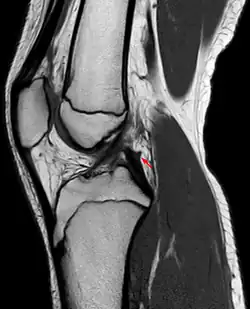

The posterior meniscofemoral ligament (also known as the ligament of Wrisberg) is a small fibrous band of the knee joint. It attaches to the posterior area of the lateral meniscus and crosses superiorly and medially behind the posterior cruciate ligament to attach to the medial condyle of the femur.[1]

The posterior meniscofemoral ligament is found in 64.4% of the subjects in MRI scan of the knee.[1]